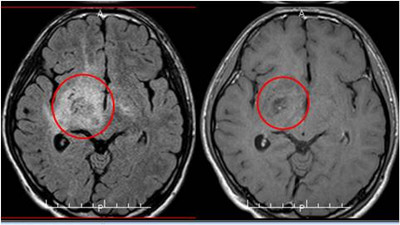

辗转多院后,经由熟人的推荐,小磊的家长找到广东三九脑科医院的蔡林波主任。入住肿瘤综合治疗中心,给小磊做了腰穿查脑脊液,HCG:39.48IU/L(0-5)高于正常,查血HCG:6.21mIU/mL(0-5)稍高于正常,查头颅磁共振示:1.右侧基底节-放射冠区、右侧视交叉及右侧大脑脚、左侧基底节区(以右侧基底节区为主)多发病变。

2014年9月 放疗前

结合小磊往期的MR片,蔡林波主任给出综合分析,考虑小磊患生殖细胞瘤可能性大,而病变位置深,活检取病理难度大,建议行诊断性放疗。靶区为肿瘤强化部及T2压水象异常信号区,单次量180cgy,900cgy/5f。